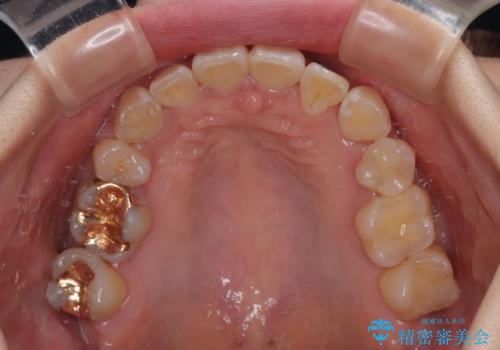

奥歯の咬み合わせ改善にはどうしても長期間を要します。

3年強とお伝えしておりましたが、予想通り3年3ヶ月で治療を終えることができました。